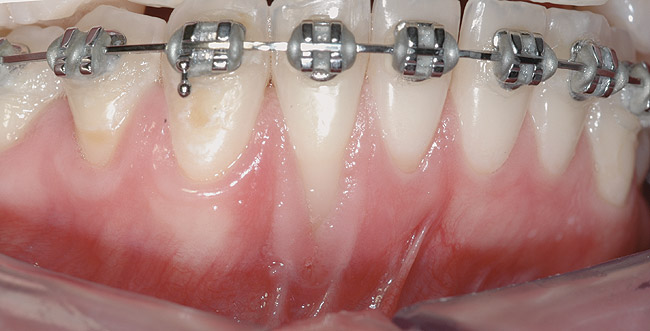

CASE 3 Fig 6. Post-orthodontic Miller Class II recession recommended for orthodontic treatment. Clinical view 5 years after orthodontic treatment showing a buccally displaced root of the lower incisor.

Figure 6

Fig 7. The CBCT sagittal view shows 4 mm tickness of bone on the lingual aspect of the affected tooth.

Figure 7

Fig 8. During orthodontic treatment showing a significant decrease of defect size.

Figure 8